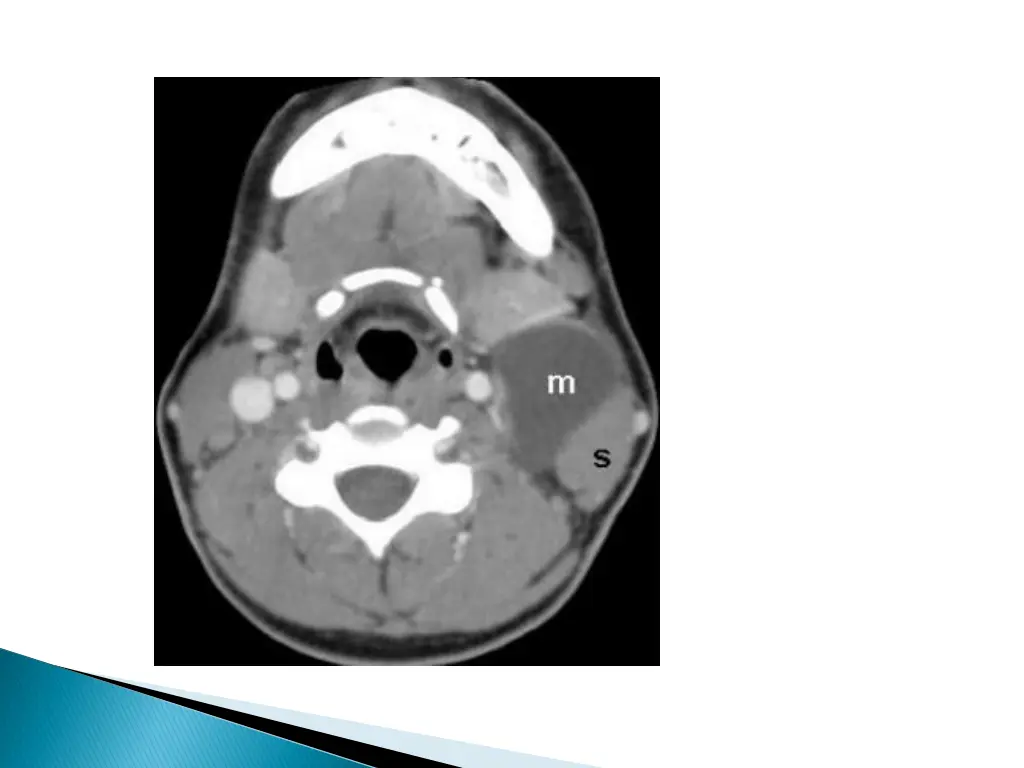

CHARACTERISTIC LOCATION : Along the anterior border of the SCM lateral to the carotid space and posterior to the submandibular gland. Displaces the carotid vessels : medially\ SCM : posteriorly or posterolaterally Submandibular gland : anteriorly May extend into the parapharyngeal space after extending through the stylomandibular tunnel and middle constrictor muscle.

MRI better depicts the deep tissue extent. Cyst fluid hypo/hyper on T1W and hyperintense on T2WI. Occasionally, BEAK SIGN : on axial CT/MRI image : pathognomic of a 2ndbranchial cleft cyst especially bailey s type III cyst It represents a curved rim of tissue or a beak pointing medially between the ECA and ICA.